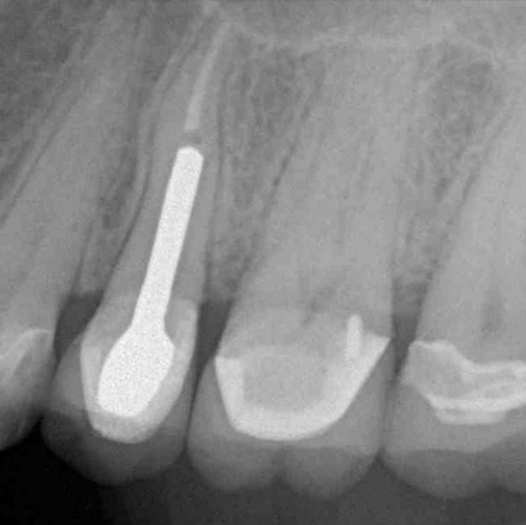

After

After Root Canal treatment